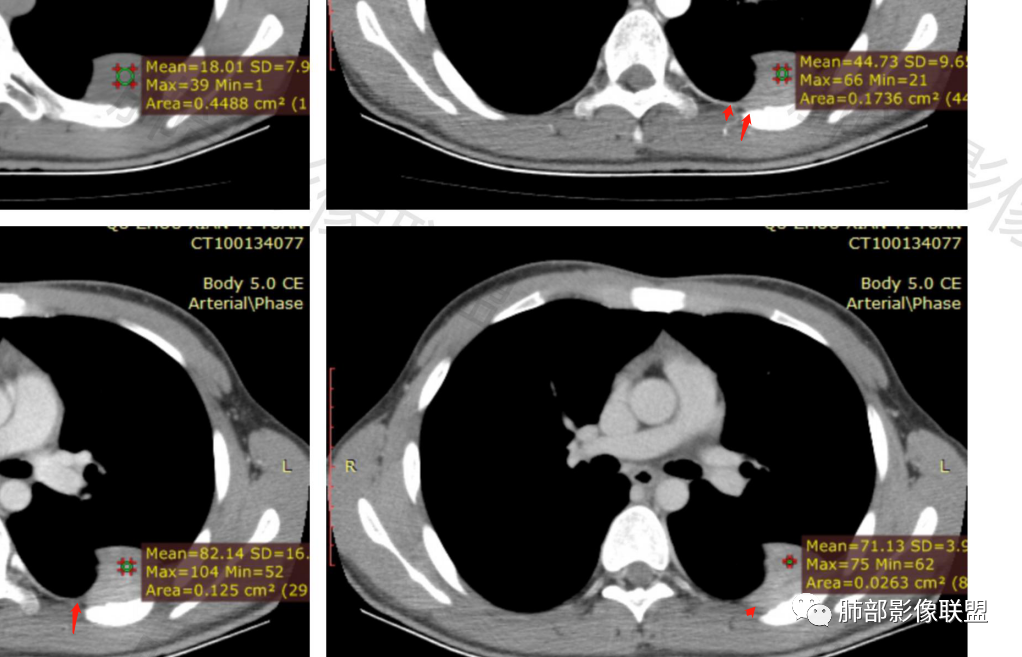

2.左侧叶间裂后缘及胸壁区不规则块影,肺组织一侧边缘光整。密度不甚均匀,未见钙化,不均匀强化,未见明确支气管及肺血管影进入,也未能显示肋间动脉进入。

3.块影有沿胸膜生长蔓延趋势,可见胸膜尾征。胸壁侧边界不清,所经两处肋骨内侧缘骨皮质吸收破坏,局部硬化,边界可分辨。肋骨未见变形膨胀或葱皮样骨膜反应。注意没有胸水。

1)形态、大小:一般为单发,较小者呈类圆形或椭圆形,较大者呈浅分叶或不规则状;大小差异较大,直径1-25cm(有2个高峰期,大多数肿瘤直径<5cm,或者>10cm),肿瘤的大小与发生部位、病程长短有关;

3)密度:CT平扫肿瘤多呈等或稍低密度;肿瘤较小者密度均匀,较大者内部密度常不均匀、见多发灶性或不规则星芒状中心低密度区(细胞稀疏区含有丰富胶原纤维易发生黏液样变性或囊性变),钙化少见。

5)肿瘤的强化程度及方式:增强扫描肿瘤早期实性成分呈不均匀斑片或斑驳样强化,多呈“地图样”明显强化,强化程度不一,可呈轻度-显著强化,静脉期持续强化,多期增强及动态增强扫描均呈“快进慢出”型强化,且强化范围逐渐增大并趋均匀。肿瘤由肺动脉或支气管动脉供血,内部及周围常见多发粗细不等强化或流空肿瘤血管影,呈蛇纹血管征。